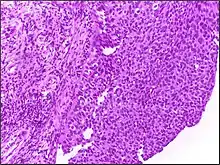

![]() | Tumor giant cell | Malignant neoplasm showing marked anaplasia. Note the marked nuclear pleomorphism, bizarre cells and tumor giant cells. | Category: Histopathology of giant cell tumors | Giant cell tumor |